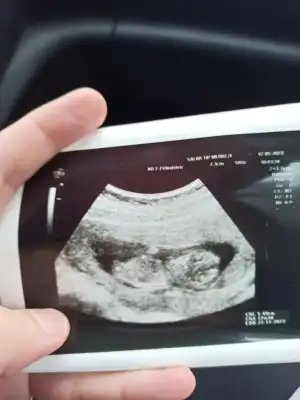

Kızlar kontrolden yeni geldik, ultrasona göre 12+3 çıktı. Doktor herhangi bir tahminde bulunmadı çok garanticidir 🤣 Sizin tahminlerinizi merak ediyorum 🙏🏻🥰

Eklentiler

• IMG_20230512_103459.webp

IMG_20230512_103459.webp

22,4 KB · Görüntüleme: 66

• IMG_20230512_103644.webp

IMG_20230512_103644.webp

18,7 KB · Görüntüleme: 66